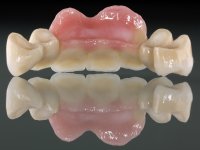

In view of the clinical situation, oral rehabilitation was proposed to improve the aesthetic appearance, but also to solve the lack of posterior teeth, seeking a functional and aesthetic rehabilitation. The plan included replacing the metal-ceramic bridge by a bridge with Zr infrastructure coated with coronary and gingival ceramics. The edentulous area of the first quadrant would be rehabilitated with 2 implants and a bridge of two elements. It was intended with this treatment plan, to recover the vertical dimension of the occlusion and to reshape the dental anatomy, thus creating a more natural aesthetic appearance.

Alginate impressions were made at both arches arcades, accompanied by intermaxillary registration relations and collecting information with facial bow facial bow. In the laboratory, a provisional bridge with 13 elements in autopolymerizable acrylic was built, in which a metallic reinforcement was included. Teeth 1.7 / 1.4 / 1.3 / 2.2 / 2.3 / 2.4 and 2.6 were used as pillars. The metal-ceramic bridge was removed after performing longitudinal cuts with diamond burs. The dental abutments were reprepared and the temporary bridge was relined in the mouth with self-curing acrylic. After confection of the provisional bridge, a gingival epithesis was made using composite resin with gingival tonality in order to function as a mock-up, which allowed the patient to preview the possibility of using gingiva shade ceramics in the final work. This option was approved by the patient. Subsequently, the placement of two implants in the first quadrant was planned and executed. The provisional monoblock was removed for placement of the implants, and after surgery was again cemented provisionally. After the osseointegration period, the impressions were made to the maxilla. In the anterior zone, impregnated gingival retraction cords were used, and in the posterior areas, kaolin paste was used. Implant printing utilized the open tray technique. The printing material used was soft and regular putty addition silicone, both fast-setting. In the laboratory, the model of provisional restorations and the gingiva epithesis mock-up served as orientation for waxing the infrastructure. The plaster work model and the waxing of the infrastructure were placed in a laboratory scanner and yielded a digital work model, in which the scanning of the waxed infrastructure was superimposed. This overlay facilitated the CAD design of the Zr infrastructure. Subsequently, the CAD drawing for a CAM milling process provided the Zr pieces. The infrastructure was pigmented with a pinkish coloration, which favors the subsequent placement of gum shade ceramic. During the modeling of the infrastructure, the need to increase the occlusal wear on tooth 1.4 was detected. This was done in the real working model cast and an acrylic wear control guide was created, which accompanied the proof of the infrastructures. Corrective wear and Zr parts test were performed in mouth. During the test, the color choice of the gum shade ceramic was reassessed. The treatment was finished in the laboratory, and after approval by the patient, was definitively placed in the mouth.